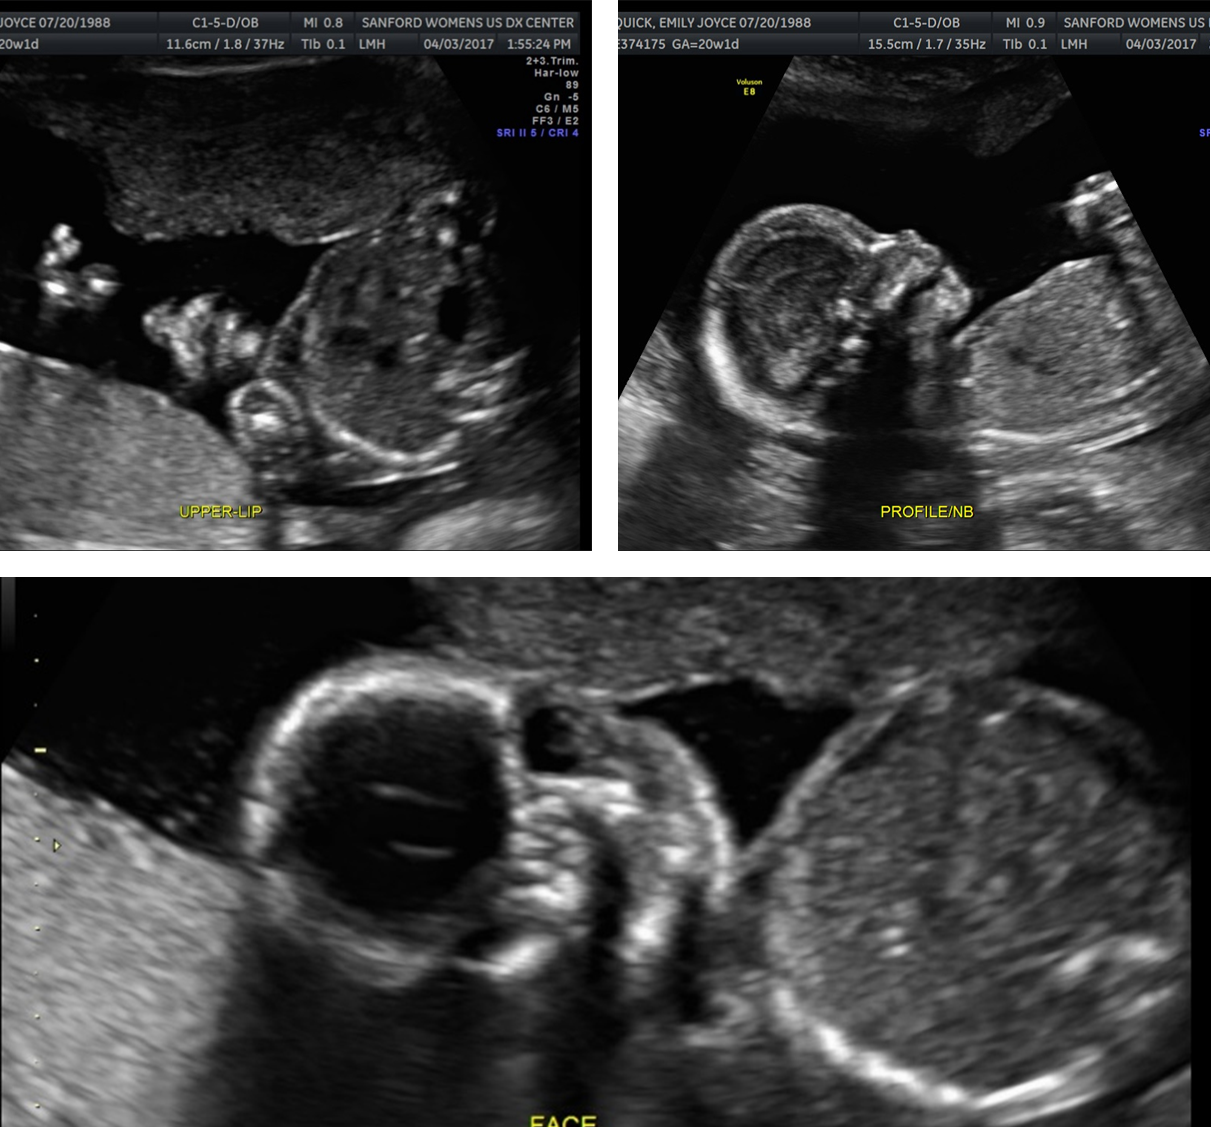

What are these images showing?

Facial Evaluation

Cleft Lip and Palate